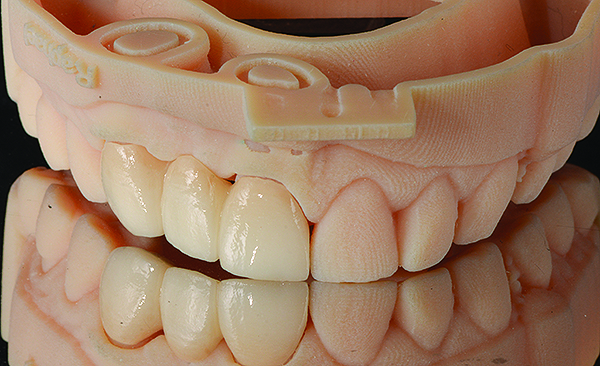

Based on the virtual plan, the treatment is carried out. An example of virtually planned and executed treatment is shown in Figure 2 through Figure 7. The patient presented with a missing maxillary right lateral incisor (Figure 2). Based on the patient’s desires, expectations, and comprehensive examination, a lithium disilicate fixed dental prosthesis (FDP) was planned to restore the missing lateral incisor. A virtual mock-up of the desired treatment plan was performed to delineate tooth length, width, and emergence profile (Figure 3). The treatment plan was then executed by preparing the abutment teeth to receive the FDP (Figure 4). An optical impression was made of the preparations and opposing teeth, and the resulting scans were virtually articulated (Figure 5). The optical impression was used to evaluate all aspects of the preparation, including finish line width and finish, path of insertion, and occlusal and axial reduction. It was also examined for the presence of undercuts, which were delineated by a red color (Figure 6). Errors in preparation design can be easily corrected and a new optical impression of the modified areas can be made without having the patient return for another visit. Once completed, the digital files can be sent to the laboratory for restoration design and manufacture, or used to design and fabricate the restoration using an in-house milling machine.14 An example of a completed restoration is shown in Figure 7.

(7.) Completed restoration seated on a model reproduced from the optical impression.

Figure 7